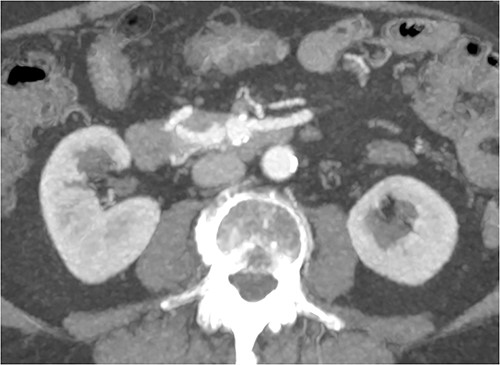

CT of abdomen and pelvis was performed, which revealed a 13 mm indeterminate lesion arising between the pancreatic uncinate process and the duodenum with coarse peripheral calcification, suspicious of primary pancreatic neoplasm or primary small bowel cancer (Figs 2–4).

Initial CT: coronal view of a 13 mm hyperattenuating region with peripheral calcification at the inferior margin of the pancreatic uncinate process and the superior margin of the duodenum.